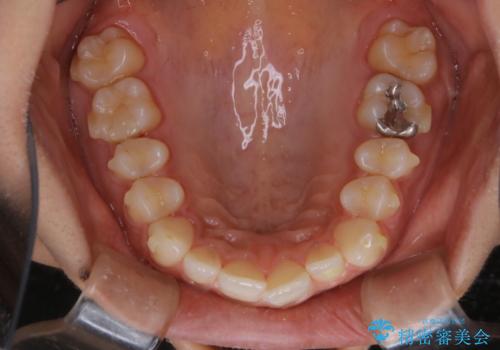

- インビザラインでの矯正治療中に、着色や汚れが気になるとのことでした。PMTC60分コースを行いました。

インビザライン治療中には、歯の表面にアタッチメント(効率的に歯の移動をするもの)を設定します。そのため歯ブラシでは届きにくい細かい部分などに、歯石や着色がついてしまうことがあります。着色などを放置していると、着色なのか、虫歯なのかの判別もしずらく正確にお口の中の状態を診断できません。

矯正治療中も定期的に歯科医院にてPMTCを受けて、お口のケアを行うことをおすすめします。